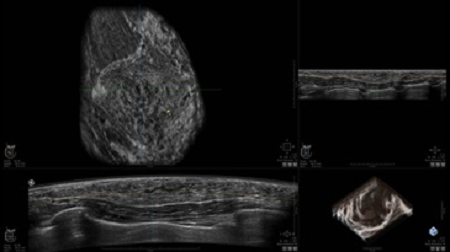

• Получение объемных 3D изображений с возможностью покадрового просмотра

• Получение изображений в поперечной плоскости (в реальном времени) и в коронарной плоскости (статическая, для указания нахождения соска)

• Отображение объемных 3D ультразвуковых изображений, которые состоят из традиционных поперечных и воссозданных коронарных и сагиттальных проекций

• Возможность отображения полного 3D изображения

• Стандартизованная ориентация изображения: «толстый срез» в коронарной плоскости; поперечная; сагиттальная плоскость; радиальный и антирадиальный поворот изображения; просмотр исключительно области интереса